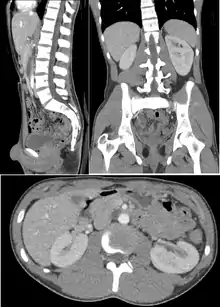

腹部和骨盆

對於腹部的疾病,X射线计算机断层成像的診斷價值極高,常用來定位腫瘤期數也用來做後續的追蹤,對急性腹痛的檢查也很有用。泌尿結石,闌尾炎,胰臟炎,憩室,腹部動脈瘤還有腸阻塞等都是可以由電腦斷層做快速診斷的疾病,它也是第一線用來診斷內部臟器外傷的利器。

口服或是直腸對比劑可視需要使用,稀釋的硫酸鋇(2% w/v)是最常用的,一般用來作大腸透視檢查的鋇劑濃度太高,在斷層影像上反而是假影,如果鋇劑有禁忌上的考量的話(例如懷疑病人是腸受傷),碘對比劑也是選擇之一,其他種類的就看目標是要對哪一個器官顯影,例如直腸的空氣對比劑(空氣或二氧化碳)用在大腸檢查,或是口服純水用在胃部檢查。

電腦斷層在診斷骨盆的應用上有限制,特別是女性的骨盆,超音波是一個替代方案。除此之外,它也可以部分應用在腹部掃描(例如看腫瘤),在評估骨折上也有用處,它也可以用在研究骨質疏鬆症,和骨質密度偵量儀一樣,此兩樣都能偵測骨礦物質的密度(BMD),也就是骨強度的指標,然而電腦斷層的結果不一定和骨密儀一樣(BMD測量黃金準則),不但貴,病人接受的劑量又高,所以不常使用。